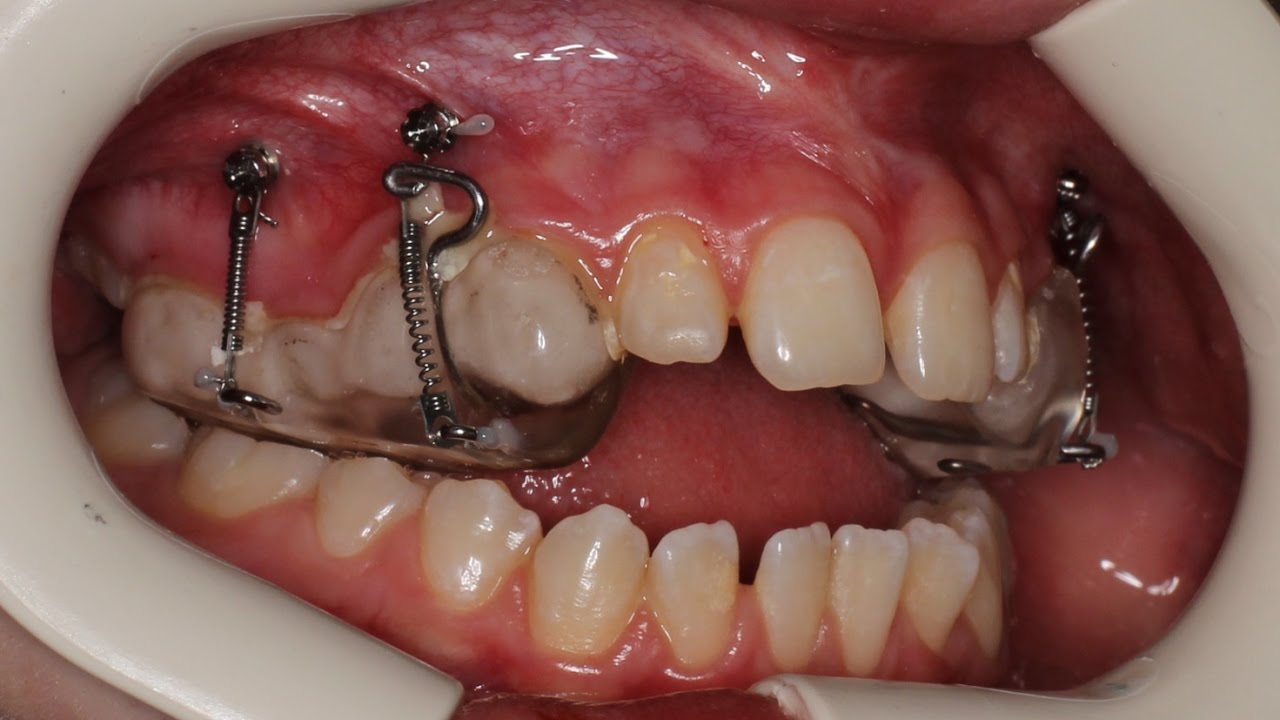

En este video su autor nos muestra un caso de una niña con mordida abierta. Tratamiento: 2,5 años con Haas para expandir el arco superior, luego le instalaron mini tornillos para penetrar los dientes posteriores. Después de eso también se usaron aparatos fijos.